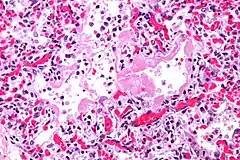

El diagnóstico se sospecha por los síntomas y los estudios de imagen. En la radiografía de tórax aparecen opacidades difusas e irregulares en los dos pulmones que se conocen como en vidrio esmerilado. El diagnóstico de certeza precisa la realización de una biopsia pulmonar y un estudio histológico de la muestra. El diagnóstico diferencial abarca distintos procesos que pueden dar manifestaciones similares, entre ellos reagudizaciones de fibrosis pulmonar, neumonía eosinofílica, neumonía organizativa criptogenética, neumonía por Pneumocystis jirovecii, neumonitis por fármacos, neumonitis por hipersensibilidad e infección pulmonar por legionella.[2]